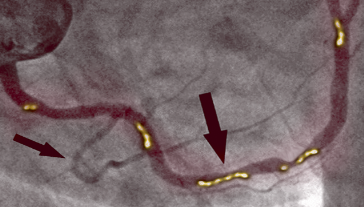

PRED KÚROU

Fotografia vľavo ukazuje stenózu pravej koronárnej artérie u 66-ročného muža, diagnostikovaná invazívnou koronárnou angiografiou. Existuje významná proximálna stenóza spôsobená kalcifikovaným plakom, ktorý blokuje prietok krvi.